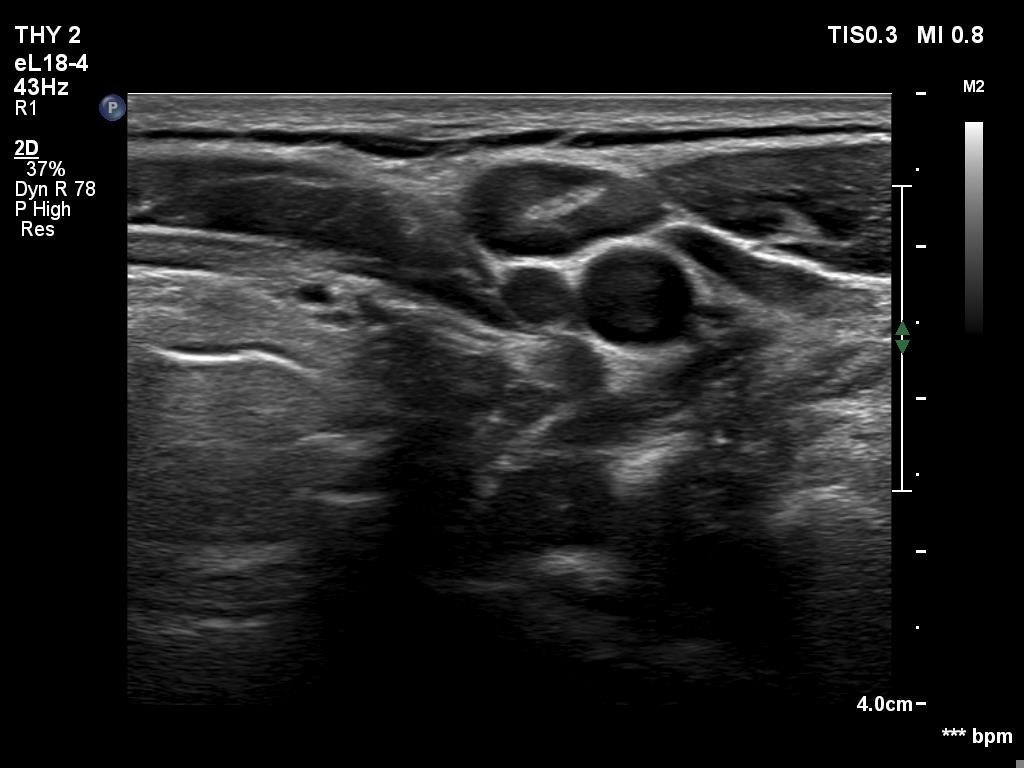

Ultrasonography. The thyroid was echonormal. There was a discrete, minimally hypoechoic area in the dorsal part of the right lobe. This was a technical artifact, caused by a connective tissue band crossing the thyroid. Although on transverse scan, the lesion looked deceptively as a discrete lesion, the real situation became clear on longitudinal scan.

The area in question did not correspond to a discrete lesion. It seemed to be circumscribed because of the presence of connective tissue running ventral which hindered the penetrance of ultrasound wave, therefore made the dorsal area hypoechoic.